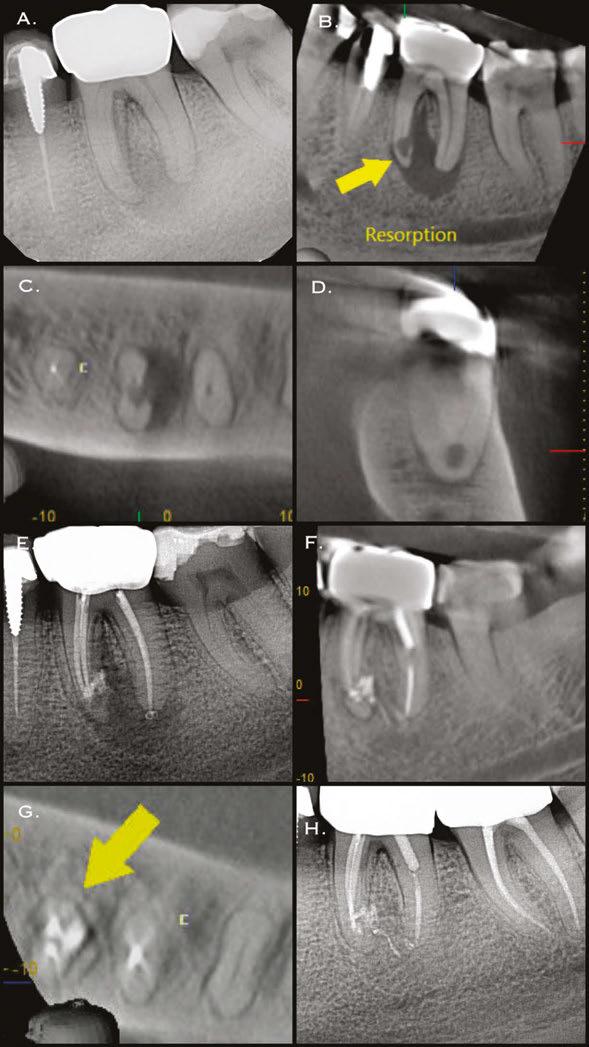

Figures 1A-1B: Two periapical radiographs of tooth No. 24 taken at different angles. Resorptive defect changes position relative to root canal, which according to buccal object rule, means defect is separate from canal and, hence, external to canal

While external root resorption comes in many forms, such as transient surface resorption, pressure resorption, external inflammatory root resorption, invasive cervical root resorption, and replacement resorption (ankylosis), internal root resorption is uniquely different. The differential diagnosis is made by taking multiple radiographs at different angles.9,10 Utilizing the buccal object rule, a lesion of internal origin will remain close to the canal regardless of the angle, while a lesion of external origin will move away from the canal depending on the angle of the radiograph (Figures 1A and 1B).

Additionally, with IRR, the outline of the root canal is usually distorted and appears contiguous with the resorptive defect, while with external resorption, the root canal outline appears normal and can usually be seen running through the radiolucent resorptive defect, as there remains a thin layer of dentin separating the canal from the resorptive area9-10 (Figures 2A-2D).

The radiographic appearance of IRR is a fairly uniform radiolucent enlargement of the root canal. There would only be alveolar bone loss adjacent to the resorption if the resorption perforates into the PDL. The best and most accurate tool we have for diagnosing IRR and determining the path of the perforating

lesion is cone beam computed tomography (CBCT). It is best to use a limited field of view (FOV), as opposed to the larger FOV used with other disciplines in dentistry. A smaller FOV increases image resolution, while at the same time providing a lower effective radiation dose to the patient. It is worth noting that in Case 2, one cannot visualize the resorptive defect from just looking at the periapical radiograph. It has been shown in countless studies that CBCT gives a more accurate diagnosis and better visualization of periapical pathology.11-13

A 41-year-old male presented with a chief complaint of pain and swelling adjacent to tooth No. 10. The patient reported a history of trauma as a teenager, though he had not experienced issues until the recent onset of pain and swelling. Clinical examination revealed tenderness on the buccal gingiva around tooth No. 10, with sensitivity to percussion and biting. A small, fluctuant intraoral swelling was noted near the apex of tooth No. 10, and the tooth did not respond to vitality testing. Radiographic examination showed a large perforating internal resorptive defect near the apical third of the root (Figure 3A). CBCT (Veraviewepocs 3D R100; J. Morita) revealed significant alveolar bone loss adjacent to the defect, extending along the entire mesial side of

Figures 2A-2D: 2A: Periapical radiograph of tooth No. 21. Large resorptive defect is noted in external cervical region. Blue arrows point to a thin layer of predentin that appears to be running through defect. Outline is what remains of root canal wall. Tooth tested vital, and diagnosis of invasive cervical root resorption was made. Due to minimal remaining tooth structure, extraction was advised. 2B-2D: Sagittal, coronal, axial slices show resorptive defect external to root canal

the apical half of the root of tooth No.10 and reaching the root of tooth No. 9 (Figures 3B and 3C).

A diagnosis of pulpal necrosis with acute apical abscess was made. All treatment options, including extraction with replacement by an implant or bridge, were discussed. The patient, motivated to retain the tooth, opted for root canal therapy and repair of the resorptive defect. Informed consent was obtained.

First visit

The patient was anesthetized with 1.7 mL of 4% articaine with 1:100,000 epinephrine (Septocaine®; Septodont®, Lancaster, Pennsylvania) via labial infiltration. Rubber dam isolation was achieved, and the tooth was accessed using a No. 2 surgical length carbide round bur. Necrotic pulp was encountered. Working length was established with a Root ZX® apex locator (Morita, Tokyo, Japan), and the canal was instrumented to a size 35 .04 Vortex Blue® rotary file (Dentsply Tulsa Dental, Johnson City, Tennessee). Care was taken to ensure that the files passed through the resorptive defect and entered the apical portion of the canal. The canal was irrigated with 5.25% sodium hypochlorite, and the EndoActivator® (Dentsply, Tulsa, Oklahoma) was used to sonically agitate the irrigant to promote thorough disinfection of the resorptive defect. The canal was dried with paper points, and calcium hydroxide (Ultracal™ XS, Ultradent Products Inc, South Jordan, Utah) was syringed into the canal and the defect. The tooth was then temporarily restored with Cavit® (3M ESPE, Neuss, Germany).

Second visit

Two weeks later, the patient returned for completion of the endodontic treatment, reporting that all symptoms had subsided. Clinical examination confirmed that the swelling had resolved. Calcium hydroxide was removed from the canal through instrumentation, irrigation, and activation with the EndoActivator. The canal was dried with paper points, and excess irrigant was removed using surgical suction with a micro-tip. A master gutta-percha cone was placed to the working length and confirmed with radiographic examination (Figure 3D). The canal was coated with EndoSequence® BC (bioceramic) sealer (Brasseler USA, Savannah, Georgia) to ensure sufficient sealer filled the resorptive defect. It was then obturated with gutta percha and BC sealer using the technique of warm vertical condensation (Figure 3E). The lingual access opening was restored with TPH Spectra® ST composite (Dentsply Sirona, Charlotte, North Carolina), and the patient was scheduled for recall to monitor healing.

At 1-year, 2-year, and 5-year recall visits, the patient was asymptomatic, and radiographs showed complete healing with full restoration of bone and lamina dura adjacent to the resorptive defect (Figures 3F and 3H). The patient expressed satisfaction with the outcome, having retained a tooth originally planned for extraction.

Figures 3A-3H: 3A. Preoperative periapical radiograph of tooth No.10 showing internal root resorption in apical third of root. There is significant alveolar bone loss adjacent to defect. 3B. Sagittal CBCT image of tooth No. 10 showing internal resorptive defect perforating on mesial aspect of root. Note adjacent alveolar bone loss extending proximally to tooth No. 9. 3C. Axial CBCT image of internal resorptive defect perforating on mesial aspect of root. There is thin layer of circumferential dentin remaining and extensive alveolar bone loss adjacent to the defect. 3D. Periapical radiograph showing gutta-percha cone fit. Gutta-percha cone passes through resorptive defect to contact apical portion of root canal. 2E. Immediate postoperative periapical radiograph of tooth No.10 once root canal was completed and resorptive defect was restored. 2F. Two-year follow-up showing complete healing of radiolucency adjacent to defect and reestablishment of PDL. 2G. Two-year follow-up CBCT. Coronal slice showing complete healing of radiolucency adjacent to defect and reestablishment of PDL. 2H. Five-year follow-up radiograph. Patient is completely asymptomatic